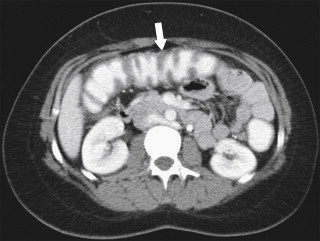

The imaging findings may lag behind the clinical features, and patients may have pronounced clinical disease without obvious imaging findings. When observed, the imaging features are similar to most other colitides. Plain radiography often demonstrates ileus and, as the disease progresses, nodular haustral thickening, often over a long segment because the disease usually presents as a pancolitis. There may be polypoid mucosal thickening representing the pseudomembranes, but this is not often observed ( Fig. 5-45 ). The disease can progress readily to frank toxic megacolon. However, it is optimally evaluated by CT, which demonstrates bowel wall thickening, mucosal enhancement, often with a mural stratification (or target sign representing unenhanced thickened submucosa surrounded by enhancing mucosa and muscularis propria), pericolonic edema, and mild ascites. The bowel wall thickening is often pronounced, more so than in other colitides, with the thickened haustra giving the appearance of an accordion pattern (also found with CMV colitis) over a relatively long segment of bowel ( Fig. 5-52 ), representing oral contrast material trapped between the bulbous-thickened haustra.

Figure 5-52, Axial contrast-enhanced CT in a 46-year-old woman with pancolitic mucosal thickening ( arrow ) due to Clostridium difficile colitis. The haustral thickening in the right colon conforms to the “accordion pattern.”